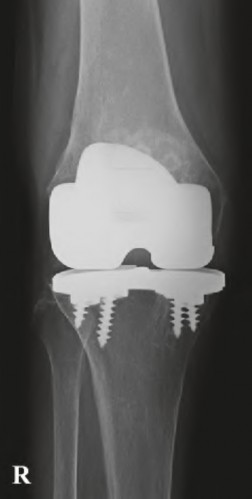

During a revision total knee arthroplasty, removal of the tibial component reveals a massive contained metaphyseal defect measuring 3 cm deep, but with an intact cortical rim. According to the Anderson Orthopaedic Research Institute (AORI) classification, what type of defect is this, and what is the preferred method of management?